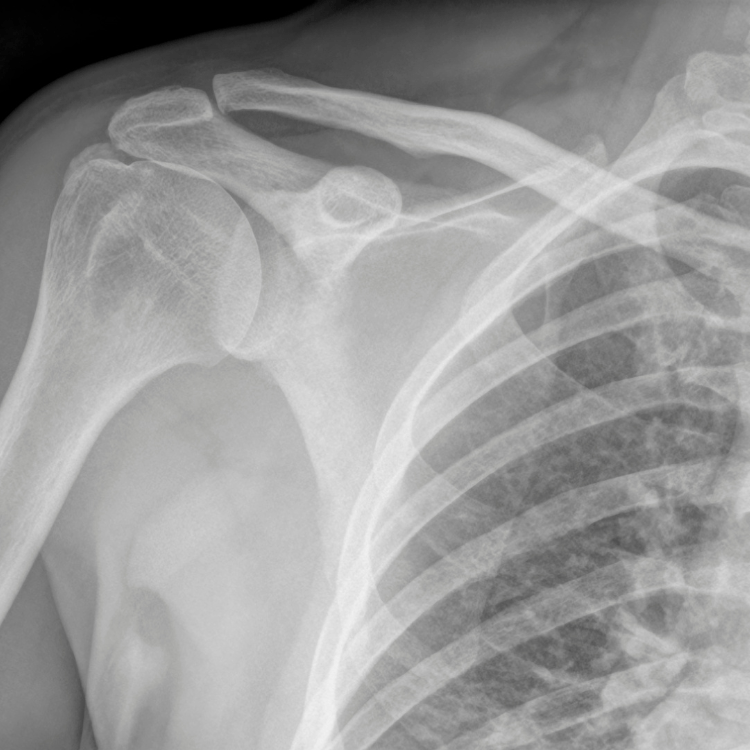

If you’ve ever experienced shoulder pain, especially when lifting your arm, putting on a jacket, or reaching overhead, you may have heard of something called rotator cuff tendinopathy (RCT). It’s a condition affecting the tendons of the rotator cuff, a group of muscles and tendons that keep your shoulder joint stable and help you move your arm.